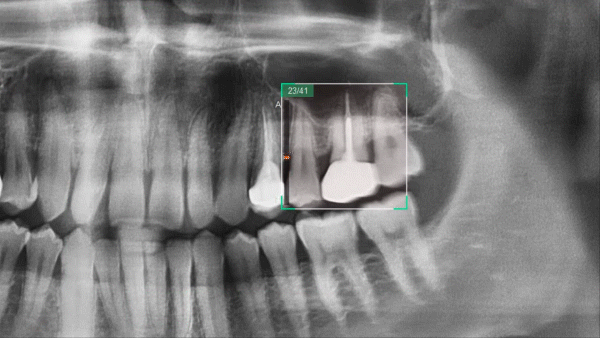

Insight Navi

Для томографа Smart Plus разработано специальное программное обеспечение EzDent-i, включающее функцию Insight Navi. Эта функция предоставляет возможность анализировать внутренние структуры зуба, перемещаясь по многослойному панорамному изображению. Благодаря дополнительным срезам, значительно облегчается обнаружение изображений мезиальных, дистальных и даже небных корней.